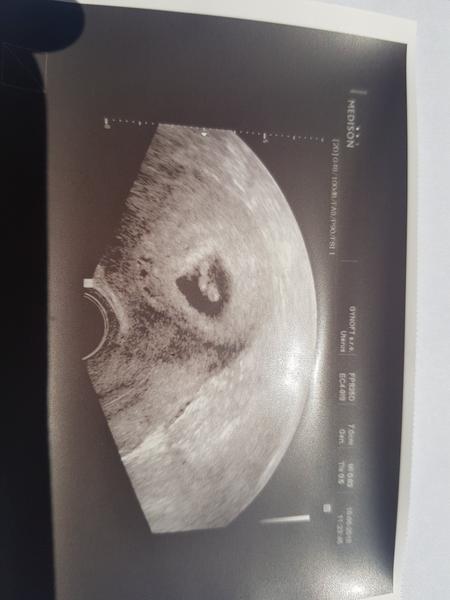

@priefi na fotce nevim.. ja to nepoznam 😓 ale dr. rikala ze srdicko bije

@priefi 7+0 a termin neresila to asi az s prukazkou dle kalkulacky 4.1. tak uvidime

Můj Dr. Podle prvního utz hned prohlásil že jde o zamlkle těhotenství byla sem 5tt a hned mě poslal na přerušení ale nesla sem a našla jineho Dr. A dnes na UTZ srdíčko a odpovídající velikost tak sem ráda že sem neposlechla a nesla na přerušení